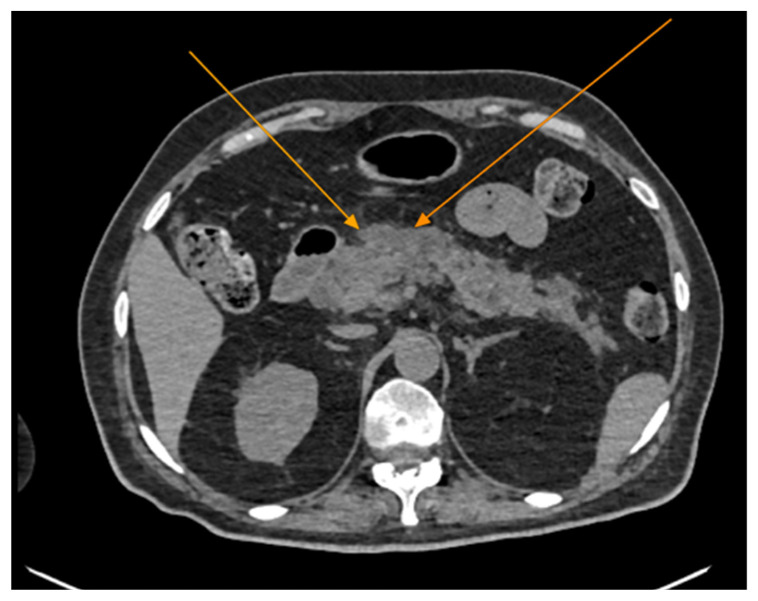

Background and Clinical Significance: Diabetic ketoacidosis (DKA) is a serious and potentially life-threatening condition, often triggered by infections or undiagnosed diabetes. Spontaneous pneumomediastinum (SPM) and pneumothorax are rare but recognized complications of DKA, possibly due to alveolar rupture from increased respiratory effort or vomiting. Sometimes, acute pancreatitis (AP) may further complicate DKA, but the co-occurrence of these three conditions remains exceptionally rare. Case Presentation: We describe the case of a 60-year-old woman without a known history of diabetes who arrived at the emergency department with abdominal pain, fatigue, vomiting, and altered mental status. Initial laboratory findings showed metabolic acidosis, hyperglycemia, and elevated anion gap, consistent with DKA. Imaging revealed spontaneous pneumomediastinum and subsequently a left-sided pneumothorax, without evidence of trauma or esophageal rupture. Epigastric pain, along with elevated serum lipase and CT findings, also confirmed acute pancreatitis. Despite the complexity of her condition, the patient responded well to supportive treatment, including oxygen therapy, fluid resuscitation, insulin infusion, and antibiotics. She was discharged in good condition after 28 days, with a confirmed diagnosis of type 2 diabetes, without further complications. Conclusions: This case highlights an unusual combination of DKA complicated by spontaneous pneumomediastinum, pneumothorax and acute pancreatitis in a previously undiagnosed diabetic patient. Because prompt intervention can lead to favorable outcomes even in complex, multisystem cases, early recognition of atypical DKA complications is critical in order to avoid misdiagnosis.